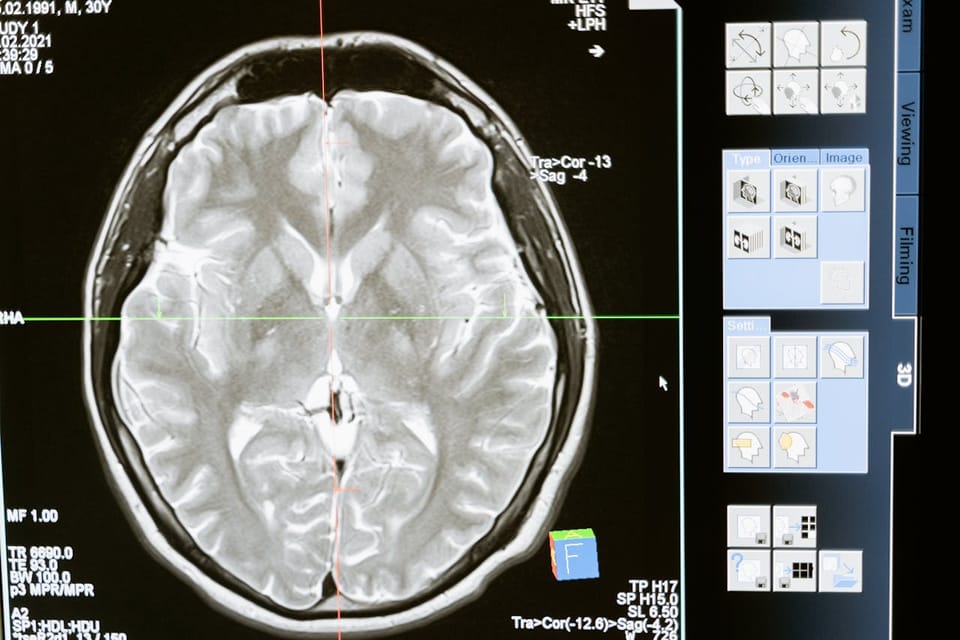

This speed is especially valuable in emergency situations where time is critical. For instance, in the case of stroke patients, immediate and accurate identification of brain abnormalities is essential to begin life-saving treatments. AI algorithms can quickly analyze brain scans, identifying issues such as blood clots or hemorrhages in real time, allowing medical teams to respond faster and with greater confidence.

Early detection of diseases is one of the most critical factors in improving patient survival rates, and AI is making significant strides in this area within radiology. By recognizing early-stage abnormalities in medical images, AI can detect diseases before they progress, allowing for earlier intervention and treatment.

One study shows that AI systems, namely machine learning and deep learning, have exhibited great success in predicting the potential occurrence of specific cancers and cardiovascular diseases. This research highlighted how AI excels at analyzing complex genetic data to accurately predict cardiovascular disease risk and identify unique genetic biomarkers, leading to more personalized treatment plans.